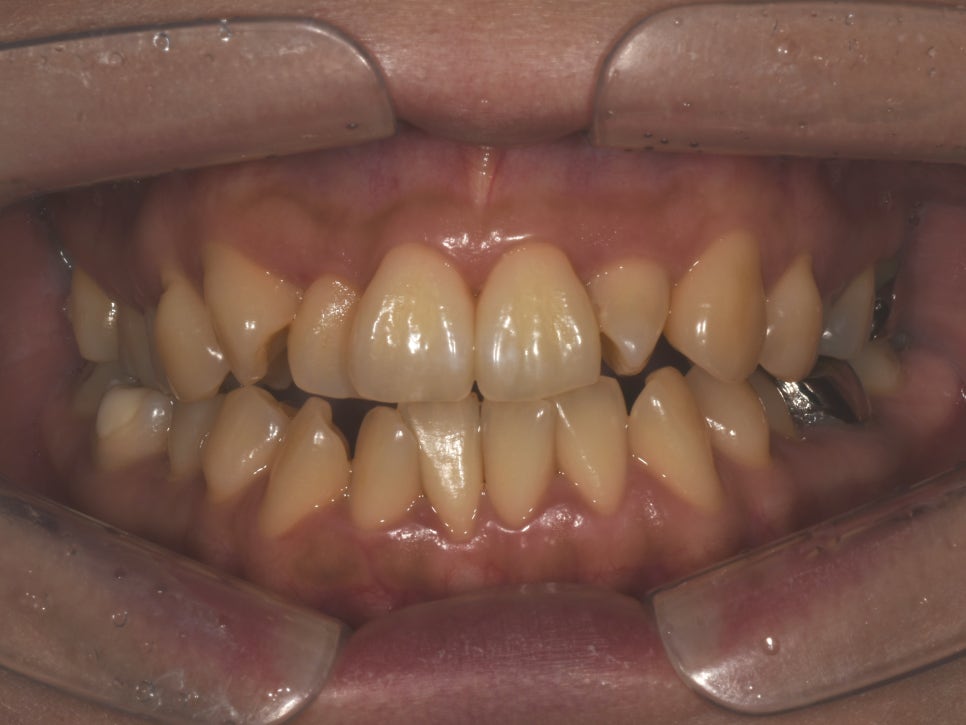

타치과 교정 후 배열은 많이 개선되었으나 탈회나 치아 사이 충치가 많이 생긴 상태

삐뚠치아 라미네이트

환자분의 동의하에 제공한 사진입니다